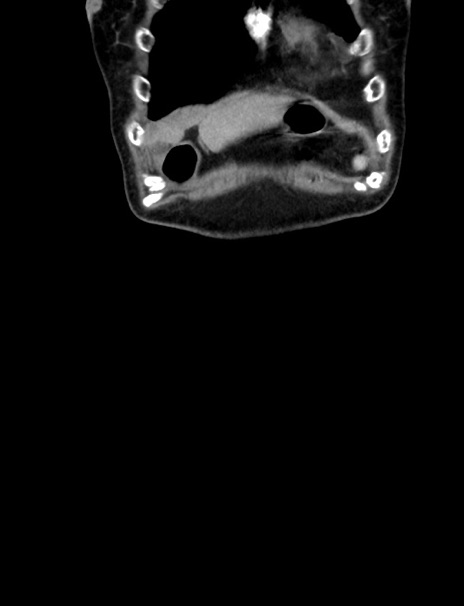

横断像